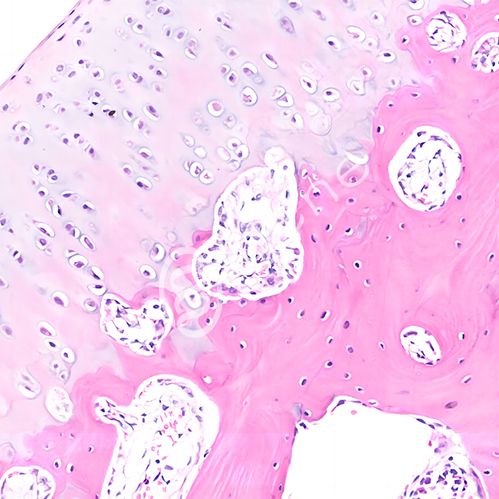

普通光学显微镜用于生物研究,其作用主要是将观察的标本放大,连接CCD后可以将观察的视野保存图片形式,以便留存和分析。

白光拍照可接收:石蜡切片、细胞爬片、冰冻切片等(切片盒保存运输)。

结果交付:3个视野,2个倍数,6张,常规同视野下200×3、400×3。默认图片不加标尺,需要请在交接单上注明。也可后期在图片的基础上加;如无拍照要求,即按常见的部位拍,例如:肝中央静脉、脑皮层海马、肾小球等,特殊染色以及免疫组化阳性部位。特殊要求请提前说明。

▶ 结果展示

200×

400×